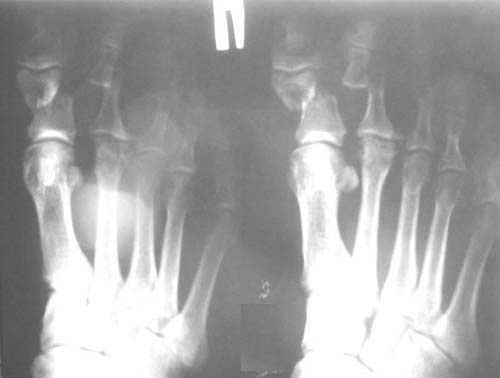

Man, 57 y.o., got a trauma in the coal mine.

Diagnosis: smash of the front parts of both feet, multiple open fractures of metatarsus bones and phalanxes of toes, contused-scalped wounds.

Right: scalped wound on the sole (10*8cm), partial injury of toes flexion tendons, incomplete tearing off of I-III toes (on the back piece);

Left: lacerated-contused wound on the back surface (4*7cm) with smashed edges, wound on the heads of metatarsus II-III bones (4*2cm), contused wound on the sole (2*1cm).

Left foot

Right foot